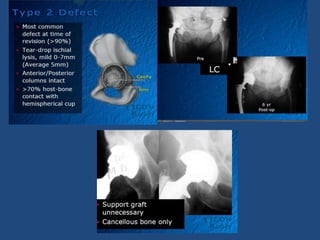

Type 2 defect management

• Uncemented

hemispherical cup with

screws

• Graft cavitatory defects

• +/- structural allograft to

restore bone graft

Type 2 defectmanagement • Uncemented hemispherical cup with screws • Graft cavitatory defects • +/- structural allograft to restore bone graft • Identifying true acetabulum  Obturator foramen/ Pubis/ Ischium  Greatest bone volume

• 18.

Medialisation of innertable • Expansion Ream at true acetabulum until ant& Post column contact • Hemispherical shape • Insert trial • Assess bone loss – Structural allograft – Porous metal augument

• #16 Migration of the component occurs superior and lateral because the acetabular rim is deficient.

• #17 Reconstruction of these defects is similar to the treatment of protrusio acetabuli in the setting of a primary arthroplasty. Radiograph demonstrating a Type 2C acetabular defect. The teardrop is obliterated and the component has migrated medially past Kohler’s line.